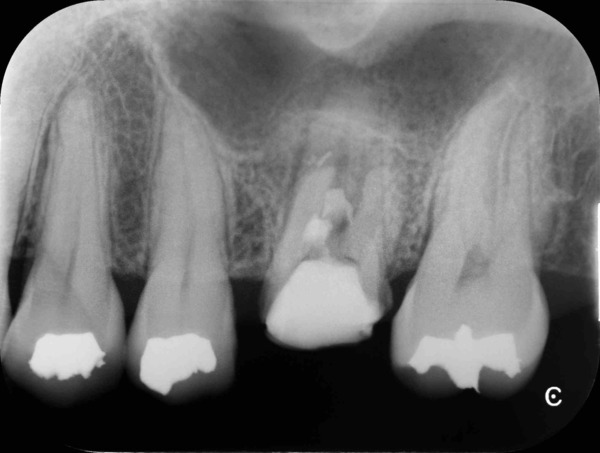

術前のレントゲン写真とCT画像、お口の中の状態です。左上の前から6番目の歯(#26)です。歯の残りも少なく、歯肉にニキビのような膿の出口があります。

治療を開始し仮の蓋を除去すると歯の中にプラスチックの材料が残っていました。その材料を取り除くと穴(穿孔)を発見しました。全部で2つありました。

本来の根管とは別の部分に空いてしまった穴はそれ自体も感染しているので、よく消毒してからMTAという特殊なセメントで封鎖をします。

根の中を詰めた直後のレントゲン写真です。

術後6ヵ月のレントゲン写真と、お口の中の写真です。

ニキビのような膿の出口もキレイに消えています。

歯根の周りの黒い影(透過像)の改善を認めます。